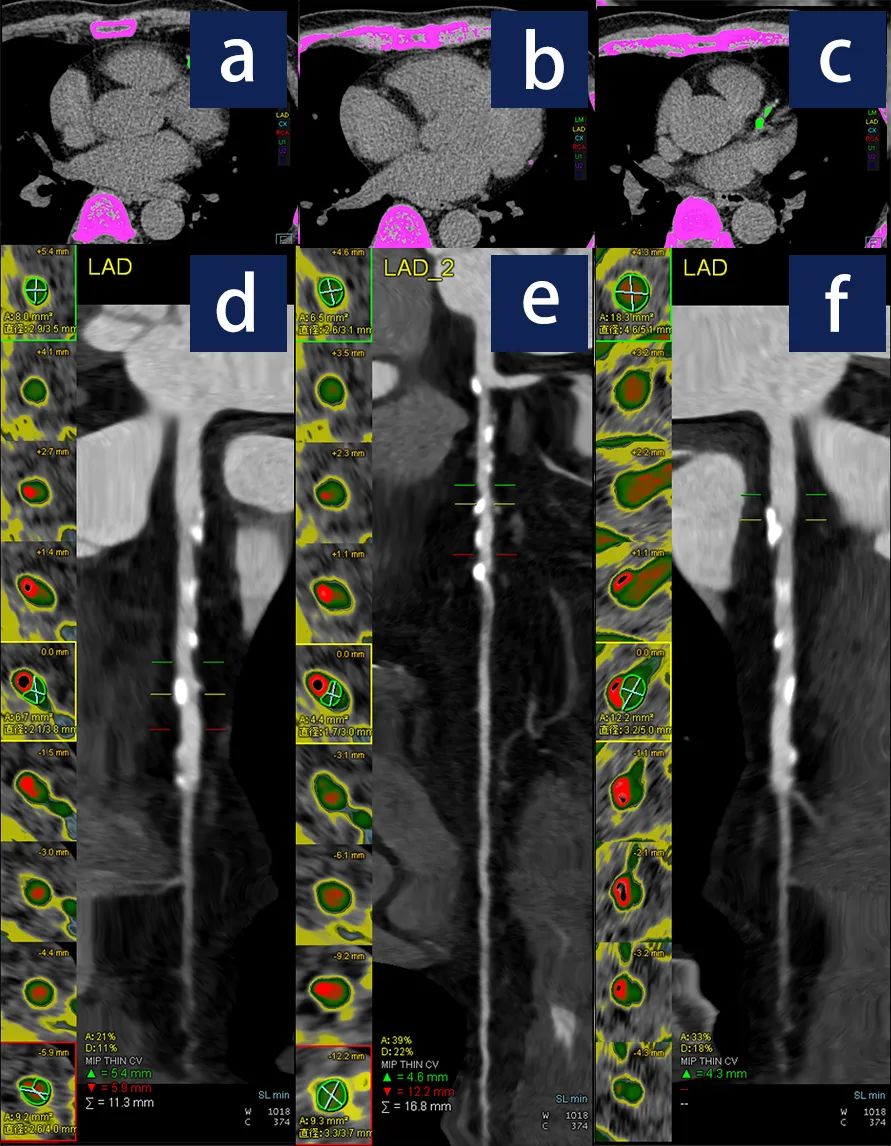

3、血管測(cè)評(píng)

我們對(duì)左、右冠狀動(dòng)脈進(jìn)行定義示蹤,可以對(duì)有問題的血管進(jìn)行測(cè)量,可以得到血管管腔的直徑、面積、進(jìn)而評(píng)估狹窄的程度和具體位置。

a、b中的綠色斑點(diǎn)表示左冠狀動(dòng)脈前降支有鈣化斑塊,c中的洋紅色斑點(diǎn)表示左冠狀動(dòng)脈回旋支有鈣化斑塊;d、e、f顯示對(duì)左冠狀動(dòng)脈不同位置進(jìn)行狹窄評(píng)估。